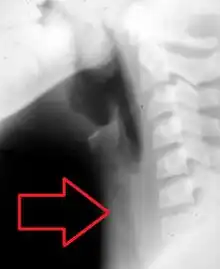

Lateral X-ray of the neck showing bacterial tracheitis with the trachea appearing hazy and debris being present within it[5]

The diagnosis of tracheitis requires the direct vision of exudates or pseudomembranes on the trachea. X-ray findings may include subglottic narrowing. The priority is to secure the patient's airway, and to rule out croup and epiglottitis which may be fatal. Suspicion for tracheitis should be high in cases of onset of airway obstruction that do not respond to racemic epinephrine.